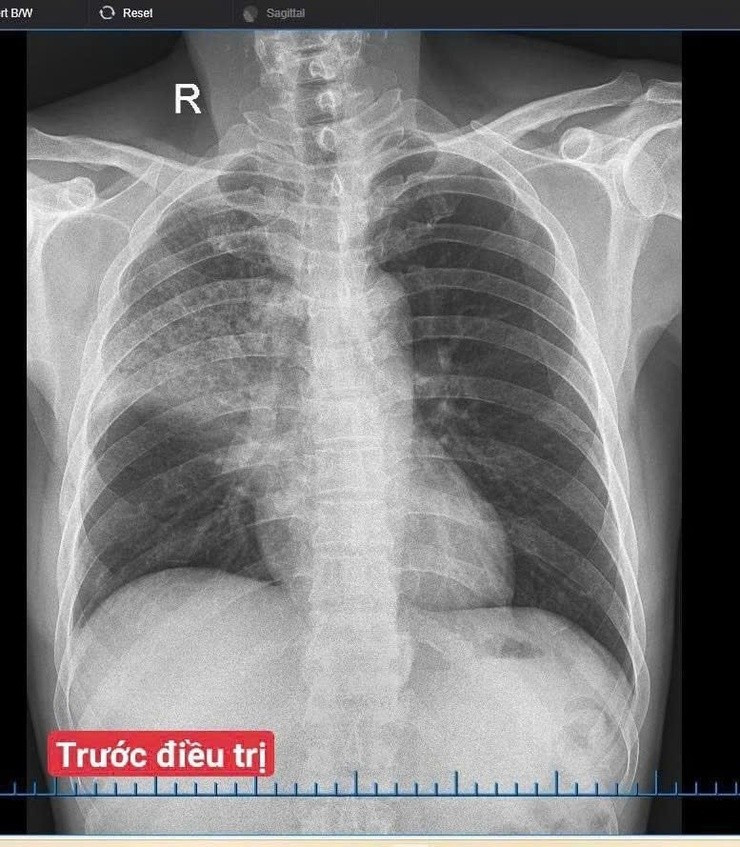

Hình ảnh trước điều trị của người bệnh. Ảnh BV

Bệnh nhân nhập viện trong tình trạng sốt cao, ho nhiều, khạc đờm đục, đau ngực và khó thở. Sau khi thăm khám, làm các xét nghiệm cần thiết, bác sĩ chẩn đoán viêm phổi cộng đồng nặng trên bệnh nhân có bệnh lý gan mạn tính. Người bệnh được điều trị tích cực bằng kháng sinh theo kháng sinh đồ, kết hợp hỗ trợ gan, bù dịch – điện giải và theo dõi sát hô hấp.